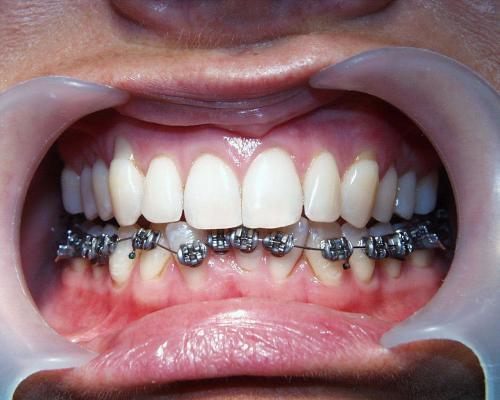

Während der Behandlung